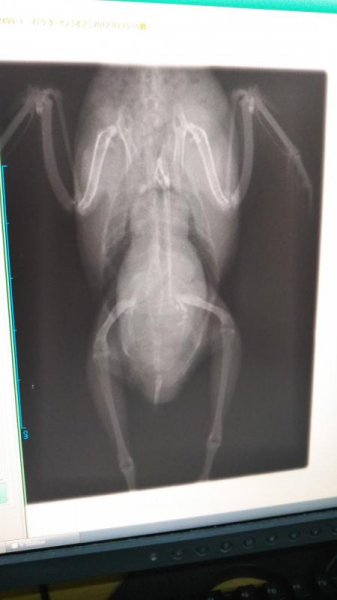

先日2022.6月10才の空ちゃんに腫瘍ができてしまい、どうしても生きて欲しくて手術を受けさせましたが。入院中に亡くなってしまいました。